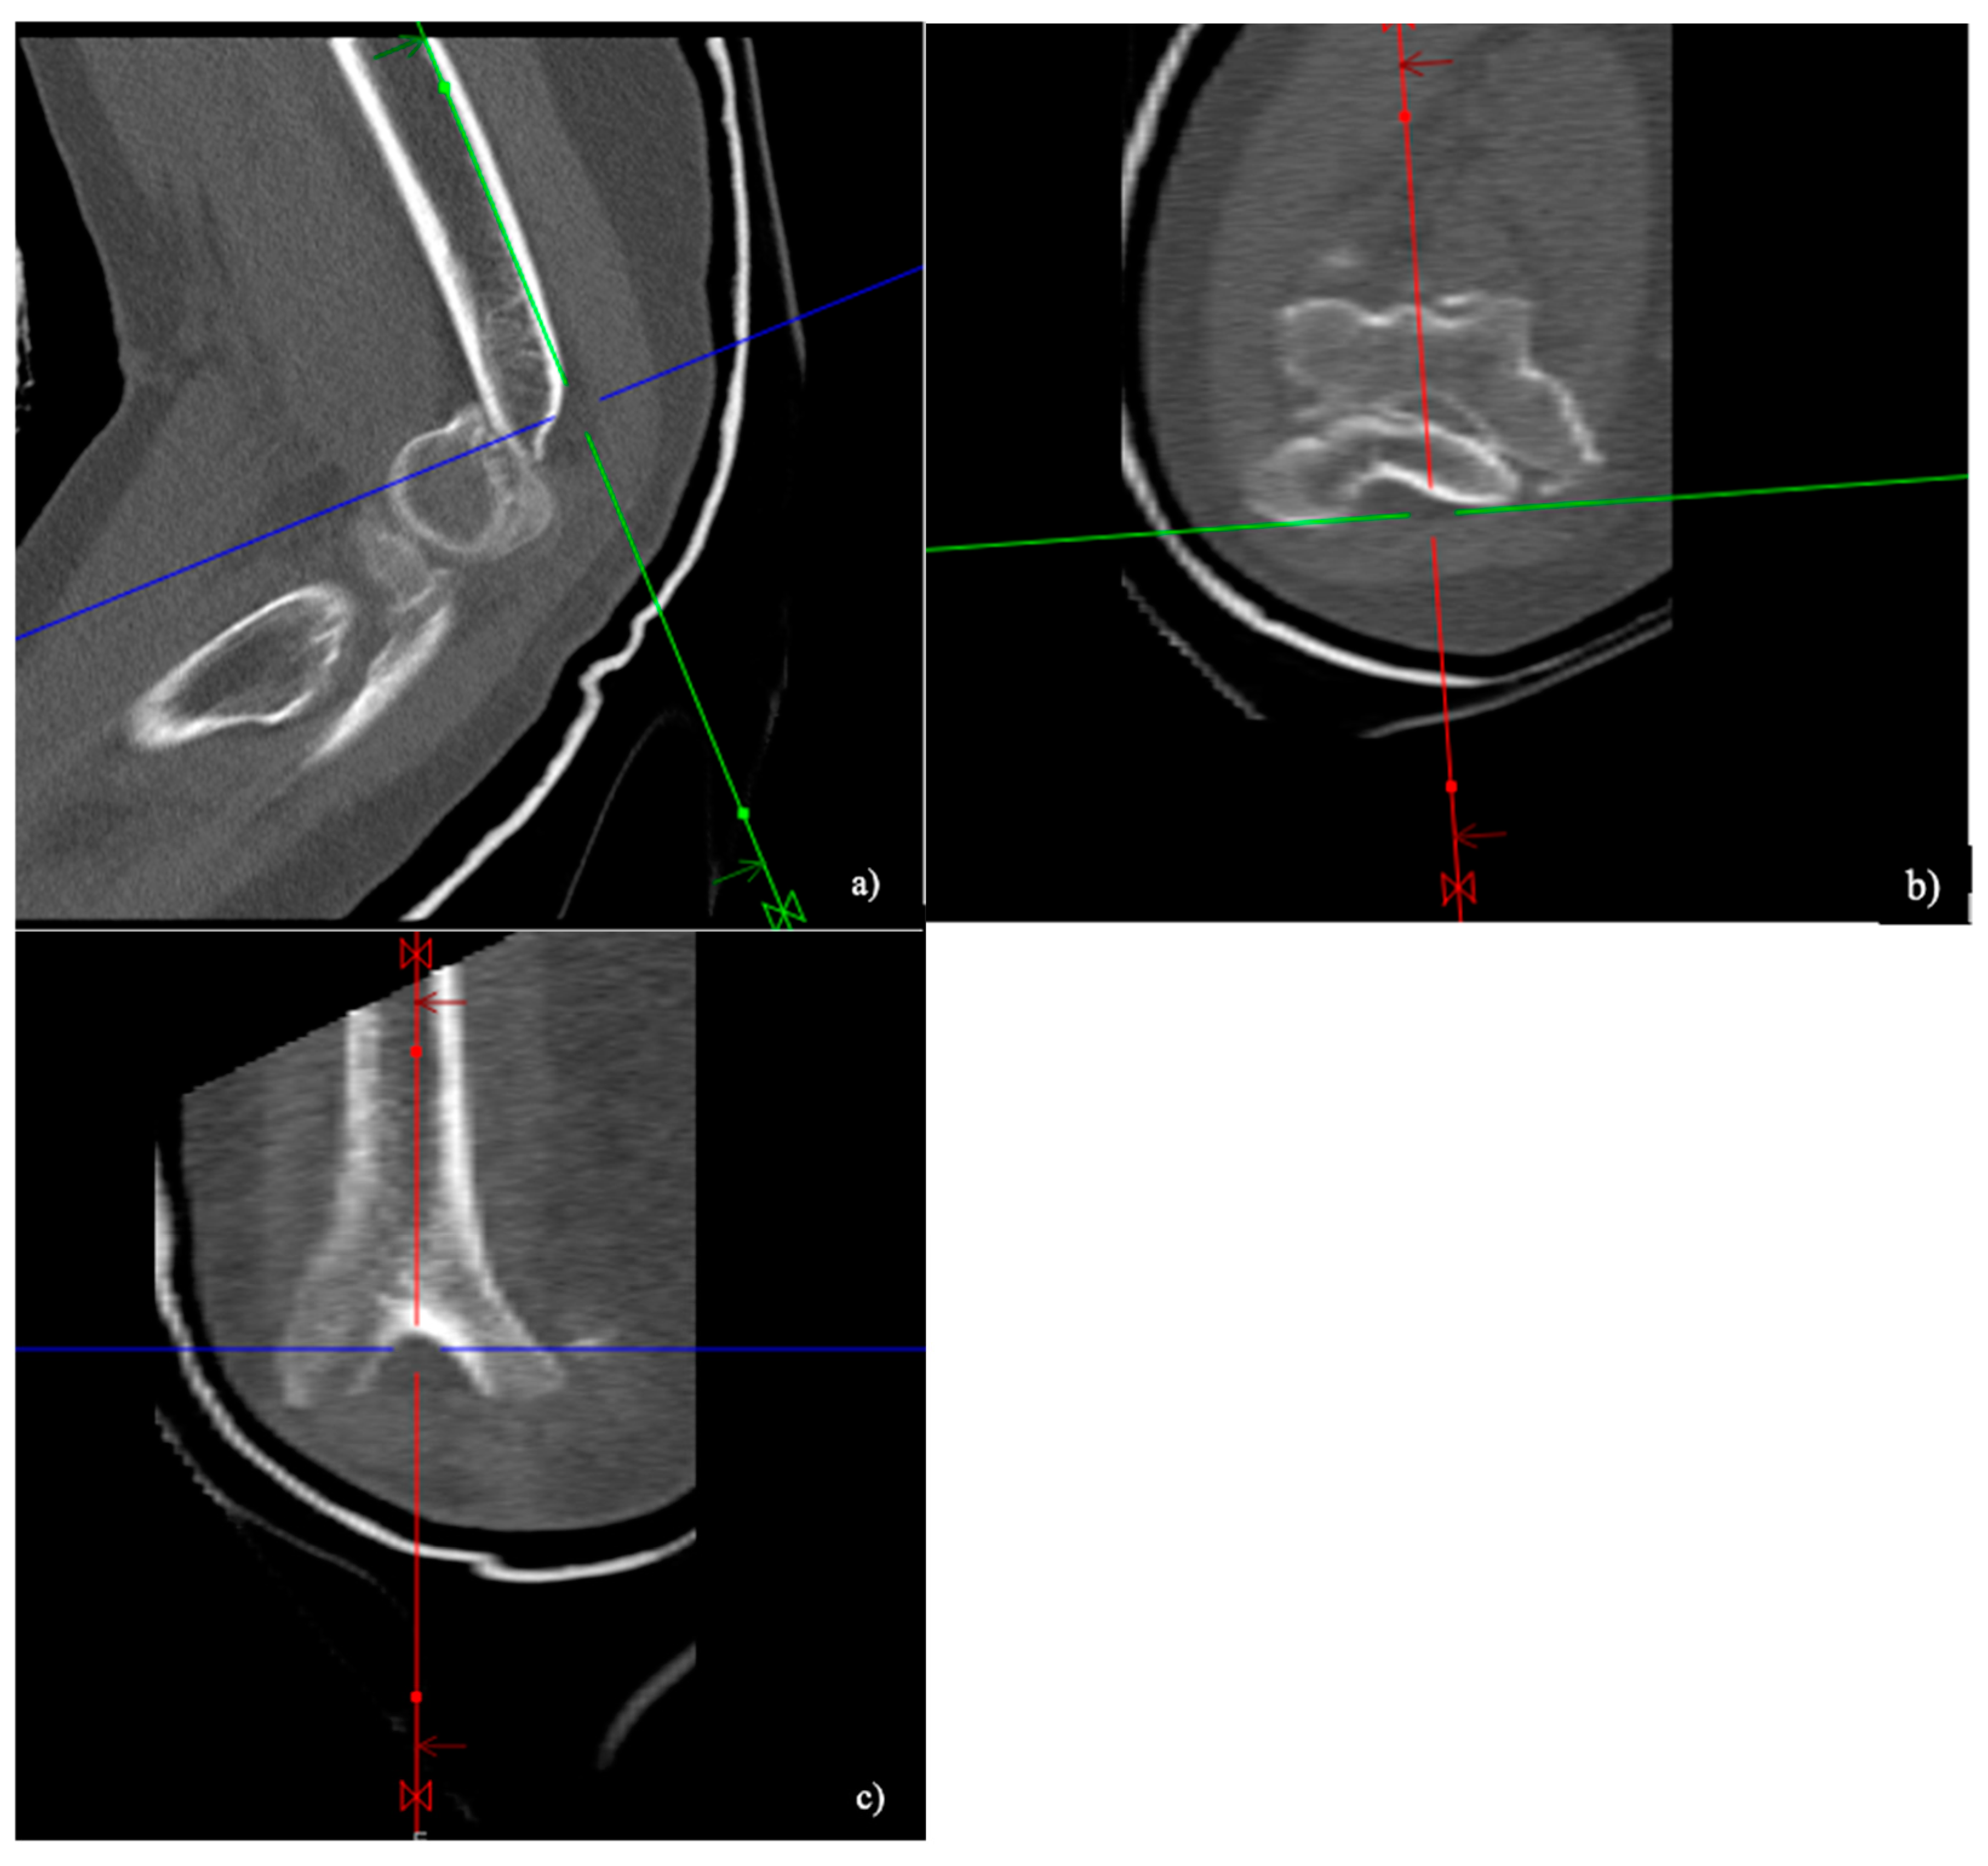

2.3. Conventional CT

2.4. CT Image Analysis